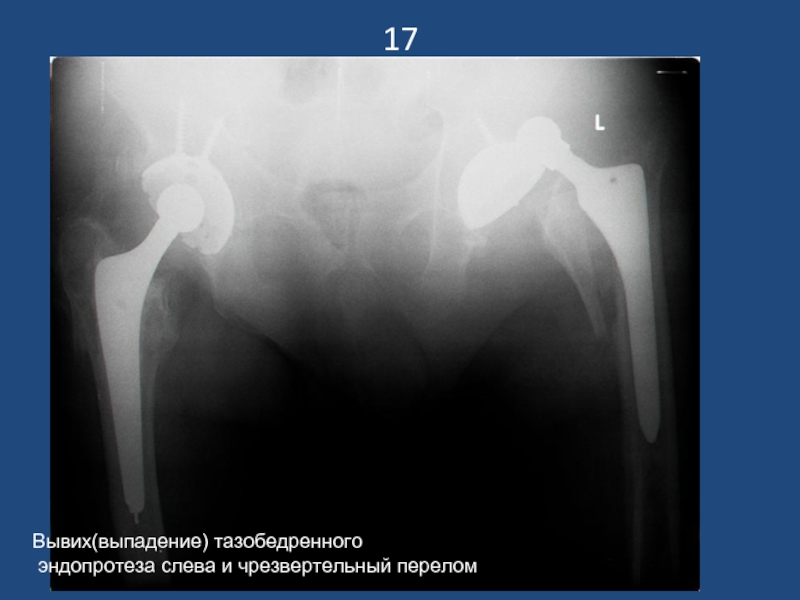

Слайд 1817

Вывих(выпадение) тазобедренного

эндопротеза слева и чрезвертельный перелом